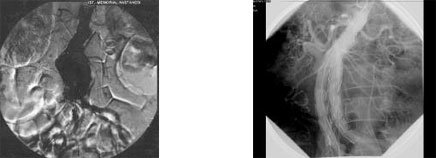

Üçüncü hastamız: Kronik lösemi tedavi gören hastamıza önce koroner bypas ameliyatı yapıldı. 2 ay sonra sonra abdominal aort anevrizmasına endostent uygulanan hasta mesane kanseri ameliyatı olmak için beklemektedir.